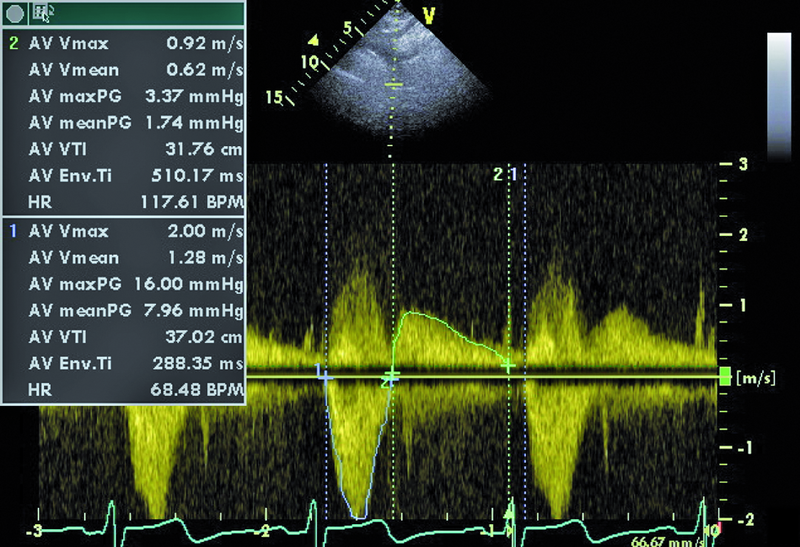

Infekcyjne zapalenie wsierdzia z zajęciem obu natywnych zastawek serca lewego nie budzi w tym przypadku wątpliwości. Proces zapalny może być rozpoznany echokardiograficznie na podstawie linijnych ech mogących odpowiadać rozerwanemu płatkowi zastawki aortalnej oraz na podstawie ciężkiego wypadania płatka zastawki mitralnej (flail), mającego zapewne charakter poinfekcyjny (ryc. 1). Stopień destrukcji zastawki mitralnej w porównaniu z zastawką aortalną wydaje się większy. Między segmentami A2 i P3 pojawia się tętniakowate uwypuklenie, będące pozostałością nacieczenia zapalnego i martwicy tkanki (ryc. 2). Tryb kolorowego doplera ujawnia dwa strumienie niedomykalności – jeden, ekscentryczny wynikający z wypadania przedniego płatka i biegnący wzdłuż bocznej ściany przedsionka (ryc. 3), i drugi pojawiający się w pewnej odległości od miejsca koaptacji, w miejscu, w którym fali zwrotnej trudno się spodziewać, jeśli struktura tkanki budującej płatek jest nienaruszona (ryc. 3, 4). Strumień niedomykalności mitralnej ma w tym wypadku charakter ostry i trafia do nieprzygotowanej i niepowiększonej jamy lewego przedsionka (ryc. 3, 4). Umiarkowana dotychczas niedomykalność aortalna, którą chory przez wiele lat dobrze tolerował, się nasiliła. Dowodem na to jest krótki czas spadku gradientu ciśnień aorta – lewa komora (poniżej 200 ms) (ryc. 5) oraz wyraźny sygnał wsteczny holodiastoliczny w aorcie zstępującej, świadczący o wysokiej wartości frakcji niedomykalności aortalnej (iloraz całki prędkości wypływu krwi na obwód i prędkości fali wstecznej 83%!) (ryc. 6).